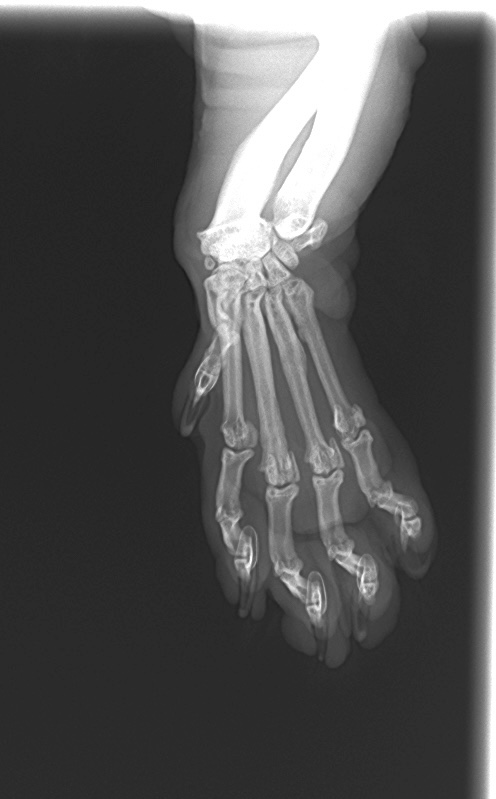

先日、左前肢の跛行を主訴に来院された猫ちゃんをご紹介します。

レントゲンで確認してみると、、、

中手骨の骨折が認められました。(第3-5指)